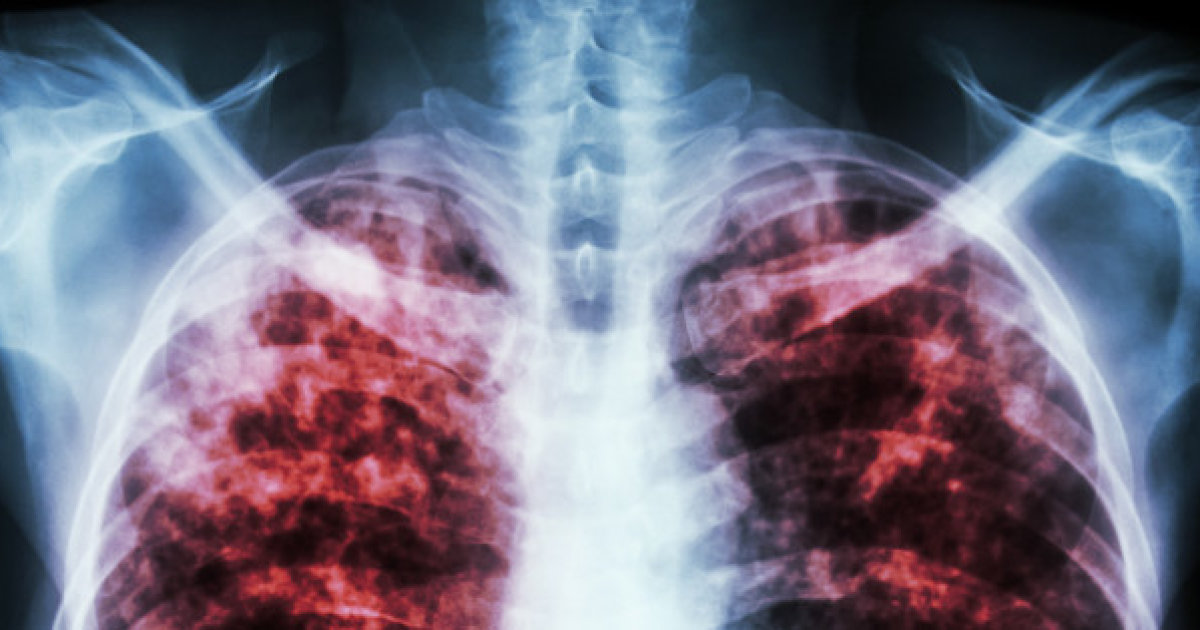

Berylliosis is a type of poisoning caused by the implantation of a toxic substance called beryllium into an individual's skin, or by the inhalation of beryllium vapors or dust. Berylliosis is a disease that is most often the result of occupational exposure to the metallic element of which is utilized in high-technology ceramic, electronic, dental alloy preparation, and metal extraction industries. Symptoms that occur in individuals affected by both acute and chronic berylliosis include breathing difficulties, sore throat, coughing, rhinitis, runny nose, chest pain, fever, night sweats, fatigue, weight loss, lymph node enlargement, and tracheobronchitis. Most symptoms that manifest in berylliosis patients branch from the effects of severe lung damage resulting from the widespread inflammation caused by exposure to the toxin beryllium. There are numerous other diseases and disorders with similar manifestations to berylliosis that should be considered prior to diagnosis.

Sarcoidosis is an inflammatory disorder that produces various symptoms that also occur in berylliosis patients. It is a disorder that happens when small nodules abnormally develop in specific organs throughout the affected individual's body. The cause of sarcoidosis is not clear, but it is known to be associated with the patient's immune system responding abnormally to an unknown substance. Numerous chemicals, infectious agents, dust, and an inappropriate reaction to specific proteins in the body are thought to be possible triggers for this reaction by the immune system. The most common organ in the body to be affected by sarcoidosis is the individual's lungs. The nodules made up of granular white blood cells from the immune system form in the individual's lungs, and they interfere with the normal function and structure of the lung and its parts. The symptoms of sarcoidosis are tightly associated with the organ and organ systems of which the nodules develop. General symptoms that mimic those of berylliosis include fatigue, weight loss, dry cough, breathlessness, enlarged lymph nodes, and chest pain.

Hypersensitivity pneumonitis is a form of lung inflammation that affects the alveoli (tiny air sacs) and the bronchioles (small airways) of an individual's lungs. This inflammation can manifest in several ways in which are similar to the manifestations of berylliosis. Chemicals or components in organic dust can trigger the hypersensitivity reaction that results in the characteristic inflammation of hypersensitivity pneumonitis. The substance the affected individual's immune system reacts to is called an antigen. The antigen settles into the alveoli of the exposed individual's lungs, where white blood cells engulf it and cause structural and functional damage to surrounding tissues. The immune system also produces antigen-specific antibodies in the affected individual's bloodstream. Symptoms of hypersensitivity pneumonitis usually occur somewhere between four and eight hours after exposure to the particular sensitized antigen. An individual affected by this type of inflammation can experience symptoms that also commonly occur in berylliosis patients, which include fever, breathlessness, persistent cough, and fatigue.

The symptoms that occur in berylliosis patients can also be indicative of an interstitial lung disease called idiopathic pulmonary fibrosis. The cause of this disease is not clear, but individuals who are regularly exposed to fumes and dust seem to be more susceptible to developing it. Genetic factors may also play a role in an individual's risk of developing idiopathic pulmonary fibrosis. This disease causes mild scarring to form at the edges of a patient's lungs that eventually worsens and moves into the center region of the lungs. Severe scarring occurs when healthy lung tissues are replaced by fibrous and dense scar tissue the body uses to heal itself from chronic damage. As the scarring in the lungs progresses, the affected individual experiences functional lung problems that stop adequate amounts of oxygen from being delivered to tissues around their body. Symptoms of idiopathic pulmonary fibrosis are similar to those of berylliosis. Indicative symptoms of both diseases include breathlessness, weight loss, dry cough, and excessive fatigue.

Tuberculosis is an infectious disease that primarily affects the lungs. The signs of tuberculosis mimic those of berylliosis, but unlike berylliosis, tuberculosis is caused by a type of bacteria transmitted through small particles in the air from an infected individual's cough or sneeze. Tuberculosis is more likely to develop in individuals who have poorly functioning or compromised immune systems. If a patient's tuberculosis is caught in time, it can be treated with medication before it is able to mutate and become resistant to the drug. Vaccines are available to prevent the spread of tuberculosis in regions of the world where it is relatively common. Tuberculosis left untreated can spread from the infected individual's lungs to the membranes that cover their brain and heart. Tuberculosis can stay latent for years in a patient until their immune system becomes weakened, and the bacteria are allowed to multiply and grow. Active tuberculosis is infectious and produces symptoms berylliosis may also produce, including chronic cough, chest pain, fatigue, night sweats, appetite loss, weight loss, and fever.